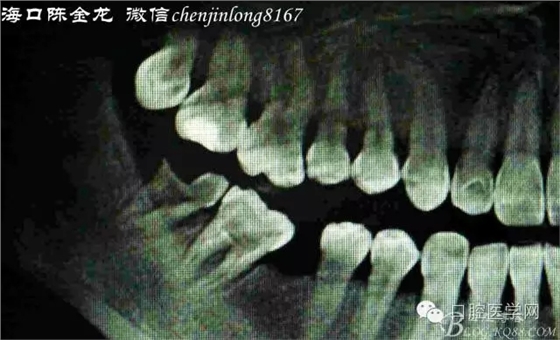

曲面片觀察

右下8形態(tài)